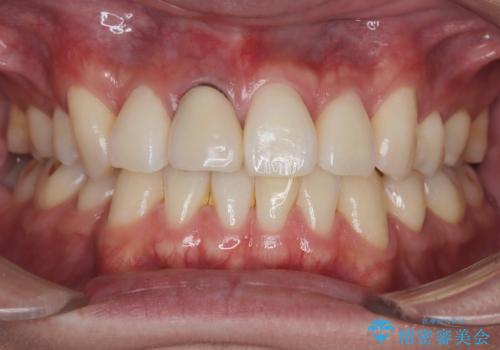

- 20代男性

- 前歯の見た目が気になるを主訴に来院された患者様です。

根管の中が空洞のままで被せ物と歯のきわも合っておらず適合が悪い状態でした。根尖部付近にはパーフォレーションリペア修復の痕がありました。バイオシーシーラーを使用しシングルポイント法で充填しました。空洞があると細菌が増える環境になってしまうので、根管治療からやり直し、緊密に充填しました。被せ物の見た目も大変満足していただけました。